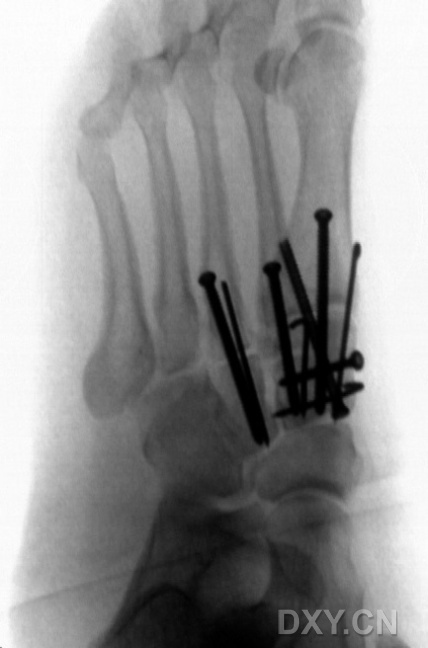

图.7

1名接受双臂外架固定患者的足正位X线片。外架的内外侧臂通过经跟骨结节的斯氏针连接